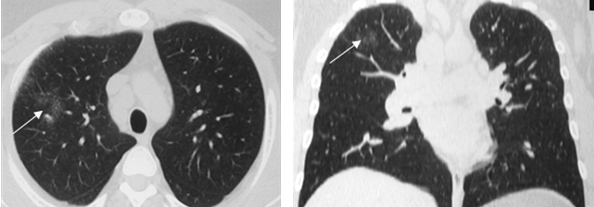

Симптом «матового стекла» (36%) визуализировался в виде небольших, ограниченных участков снижения прозрачности лёгочной ткани (рис. 2).

Рис. 2. РК-томограммы (режим лёгочного окна) пациента Г., 28 лет, с саркоидозом легких и ВГЛУ. Стрелкой указаны участки «матового стекла»

На ранних стадиях заболевания симптом «матового стекла» мог быть единственным, либо сочетаться с увеличением ВГЛУ.

Одним из наиболее часто наблюдаемых нами при КТ признаков саркоидоза являлся симптом диссеминации (70-80% случаев). При этом превалировала картина интерстициальных изменений с ретикуло-нодулярными фокусами размерами около 1-2 мм. Распределение теней было, главным образом, перилимфатическим с локализацией в средних и верхних легочных зонах (рис. 3). Реже визуализировались гроздевидные очаги округлой или неправильной формы до 6 мм в диаметре, с преимущественно субплевральной локализацией.

Рис. 3. На РК-томограммах больной Ж., 49 лет, определяется двухсторонняя диссеминация с преимущественной локализацией в среднем легочном поясе